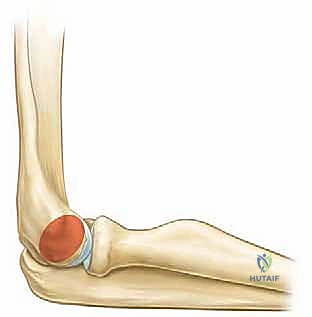

النوع الثالث (Gartland Type III)

- الوصف: كسر متزحزح بالكامل.

- السمات الشعاعية: لا يوجد أي اتصال بين القشرة الأمامية أو الخلفية للعظم. الأجزاء المكسورة منفصلة تماماً وقد تتداخل مع بعضها. هذا النوع يحمل أعلى نسبة من المضاعفات العصبية والوعائية.

- العلاج: تدخل جراحي عاجل (الرد المغلق والتثبيت بالأسلاك). في حال عدم التمكن من الرد المغلق بسبب تداخل الأنسجة، يتم اللجوء للرد المفتوح.